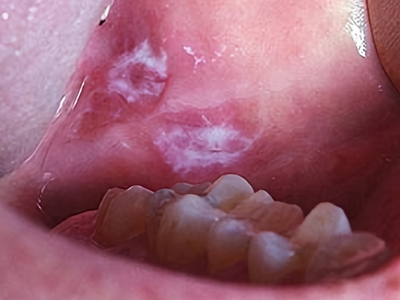

口腔

白斑

口腔白斑病一侧口腔黏膜网状白斑图

口腔白斑病表现为网状白斑,与下面的黏膜粘连很紧,强行剥去则引起出血,境界清楚,质较硬,不易推动,增厚,反复外伤可引发溃疡,因而患者出现一侧口腔黏膜有网状白斑。